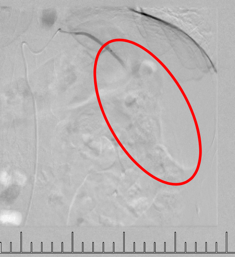

灌注藥物及栓塞后“烏云”消失

肋間動脈阻斷營養(yǎng)來源

當(dāng)日痛疼緩解